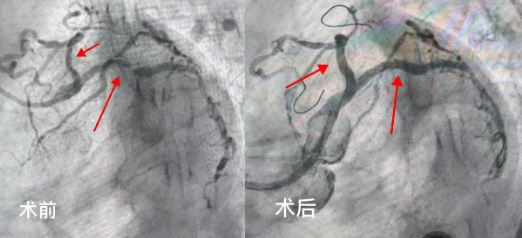

2025年5月,吉林市人民医院心内五病区收治了一位70岁的老年女性患者。该患者反复心绞痛1年,近3天症状加重。入院后,冠脉造影检查明确显示其存在严重的三支血管病变。通常情况下,冠脉搭桥手术是此类患者的首选治疗方案,但家属综合考虑患者年龄和身体状况,最终选择冠脉介入治疗。经心内五病区张金子主任团队审慎评估,决定分两次为患者实施支架植入术。

第一次手术顺利完成,在患者右冠状动脉植入两枚支架,心绞痛症状有所缓解,但仍反复发作。经过两周的精心调整,5月25日,患者再次入院接受第二次支架植入手术。然而,术后返回病区时,患者突发严重并发症——因剧烈恶心呕吐,吐出大量鲜血。由于患者既往有慢性胃炎病史,这一突发状况导致其病情急剧恶化,生命危在旦夕。